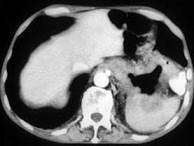

问题 男,57岁,腹部隐痛不适伴低热2月余,腋下可触及数个肿大的淋巴结,请结合图像,作出诊断 ( )

选项 A、左侧肾上腺腺瘤 B、左侧肾上腺转移瘤 C、左侧恶性嗜铬细胞瘤侵及胃脾 D、左侧肾上腺淋巴瘤且胃脾受累 E、左侧肾上腺癌并胃脾转移

答案 D